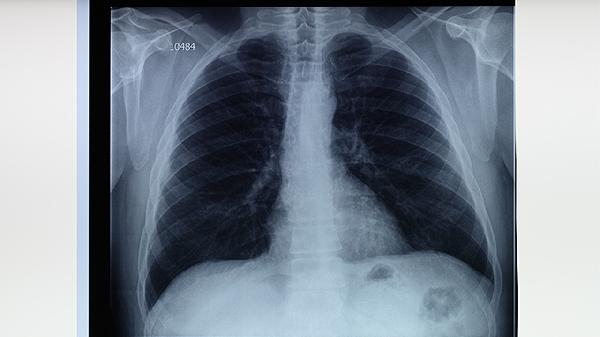

肺结核患者应严格遵循早期、联合、适量、规律、全程的用药原则,完成6-9个月的标准疗程。治疗期间保持高蛋白饮食如鸡蛋、鱼肉,适量补充维生素B族和维生素C。注意隔离消毒,避免随地吐痰,定期复查胸部影像学和痰菌检查。出现药物不良反应时及时就医调整方案,不可自行停药或减量。